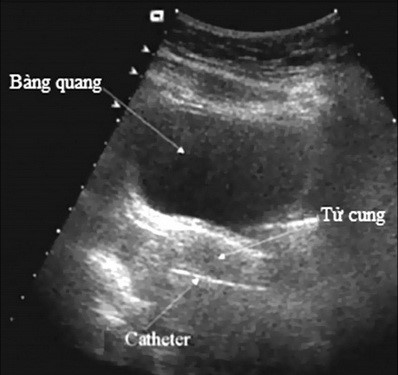

Tử cung Nhi hóa trong tuổi sinh đẻ là một thuật ngữ để chỉ những phụ nữ trong độ tuổi 16 - 45 tuổi có bất thường về kinh nguyệt và khả năng thụ thai. Cách xác định chủ yếu dựa vào sự đo đạc đường kính trước sau của tử cung trên siêu âm có chỉ số dưới 30mm, đi kèm vô kinh hay thiểu kinh.

Siêu âm.